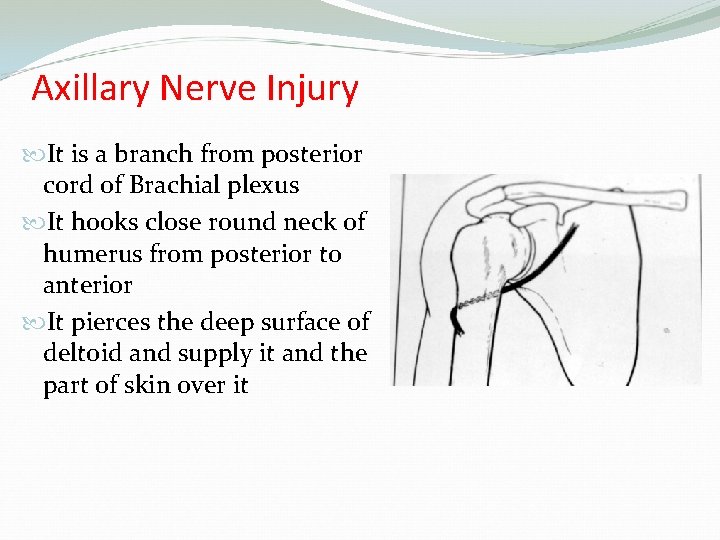

Axillary Nerve Injury It is a branch from posterior cord of Brachial plexus It hooks close round neck of humerus from posterior to anterior It pierces the deep surface of deltoid and supply it and the part of skin over it

Axillary nerve injury